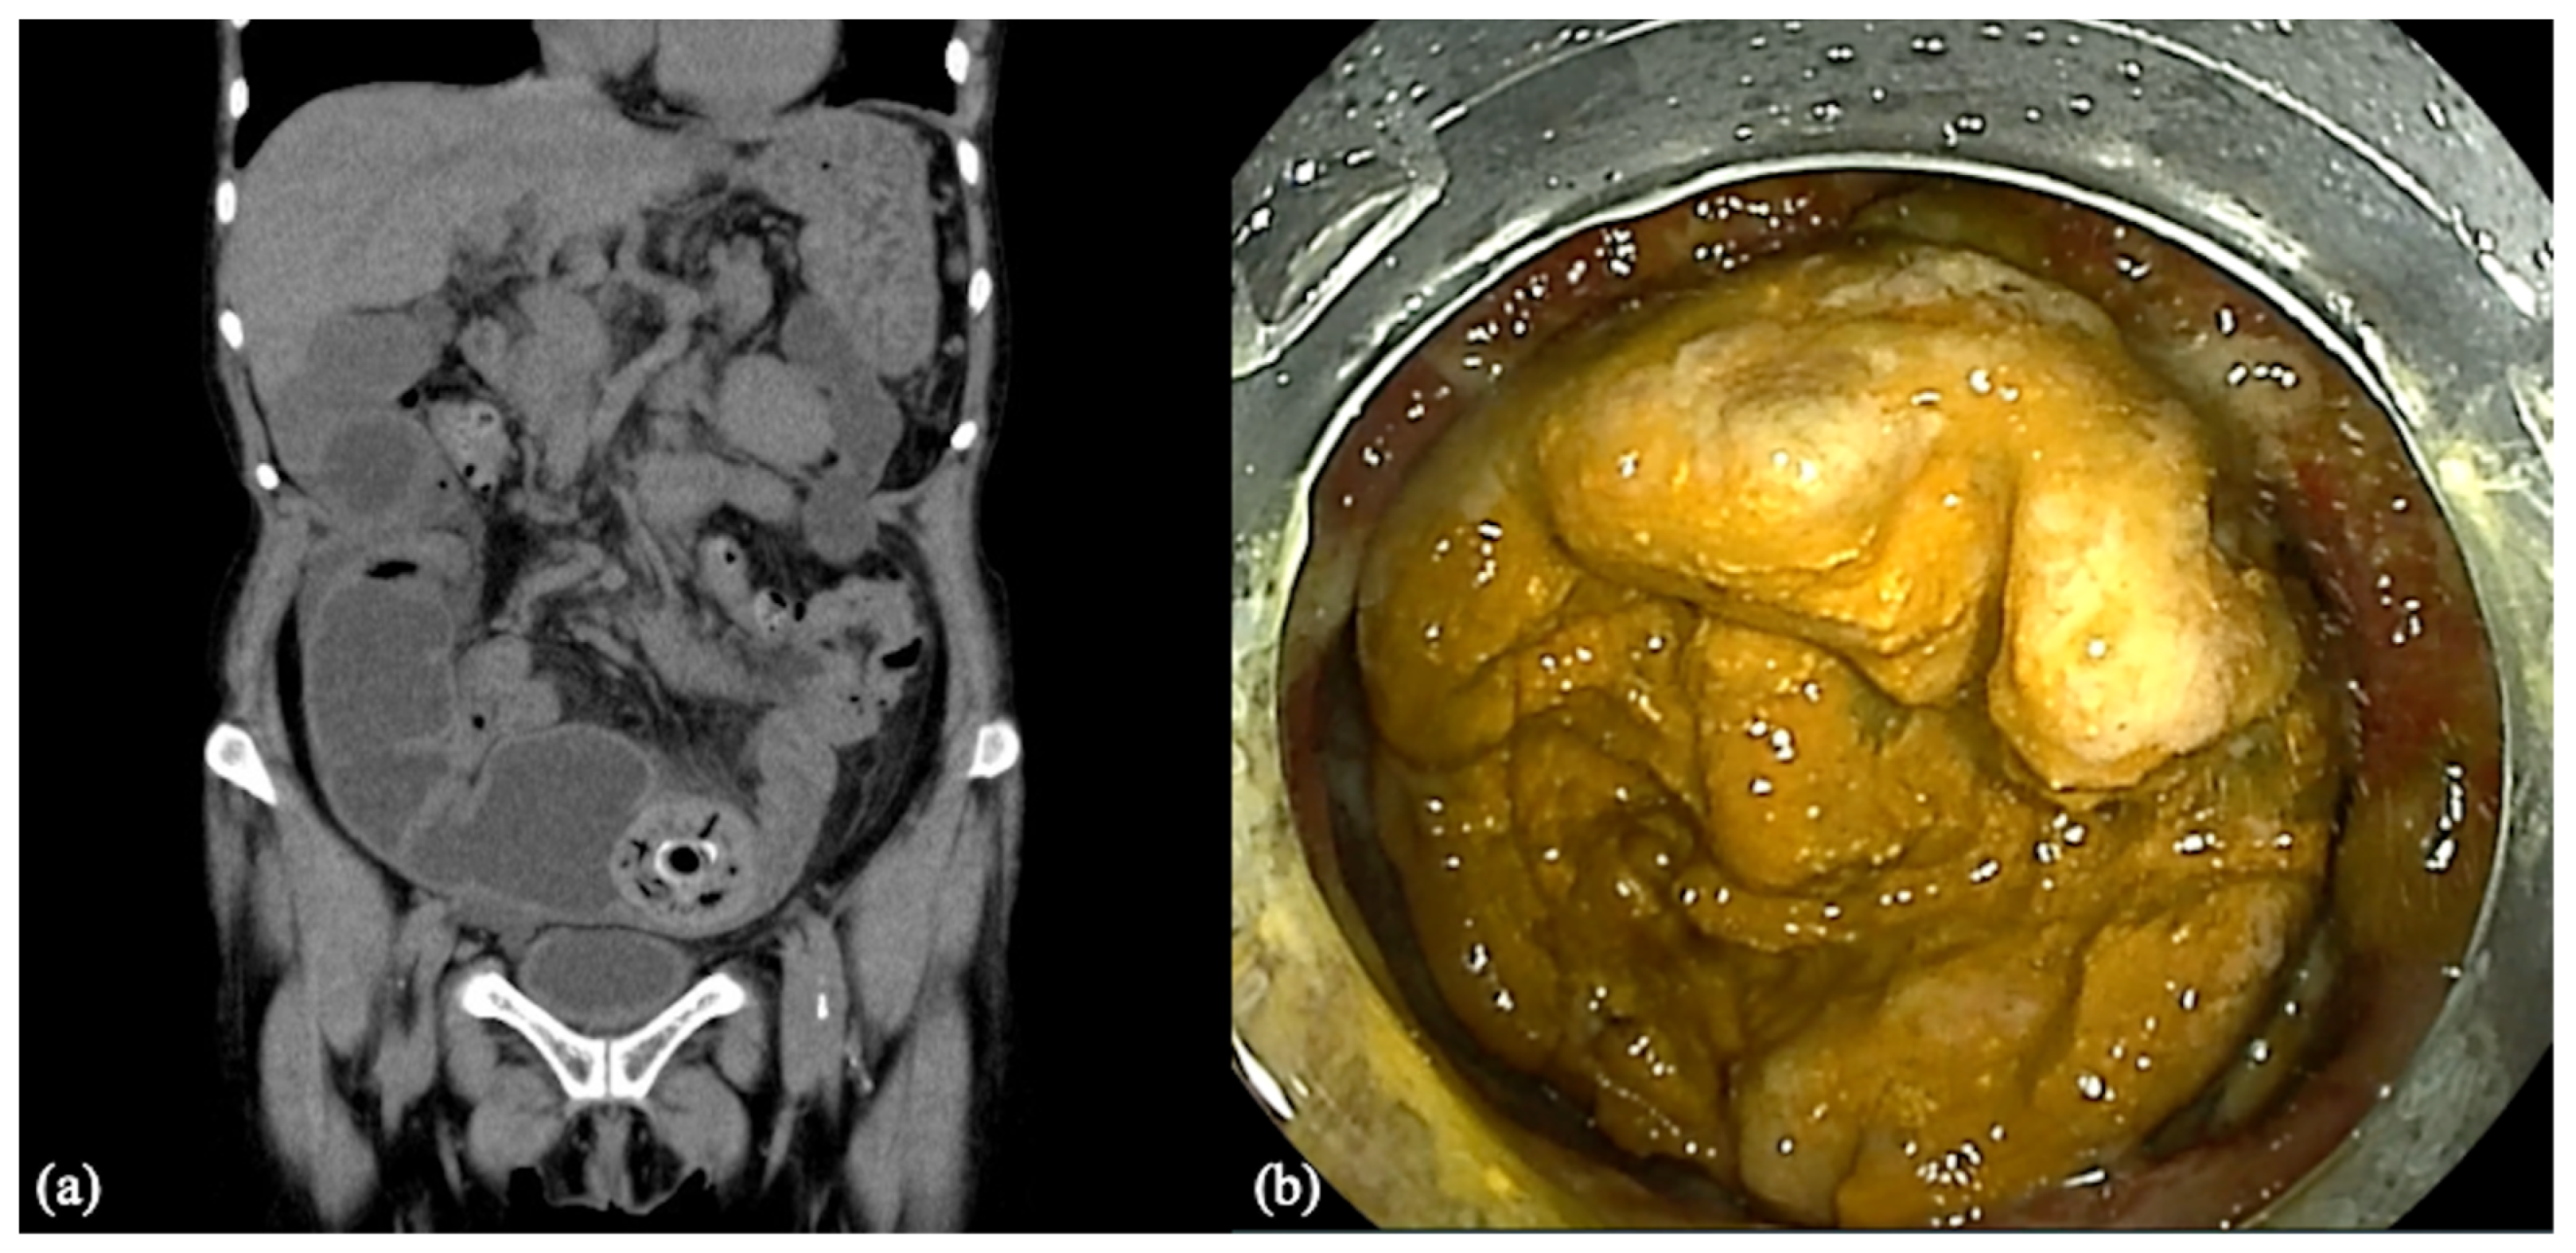

2. Case Report